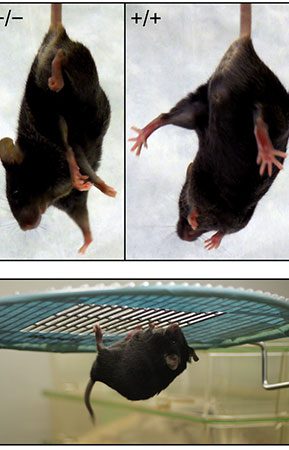

- Behavioral tests by Maurice Watermass, Shuttle Box, Openfield, Garcia, Novell Object, Elevated body

- Create and induce a variety of animal models